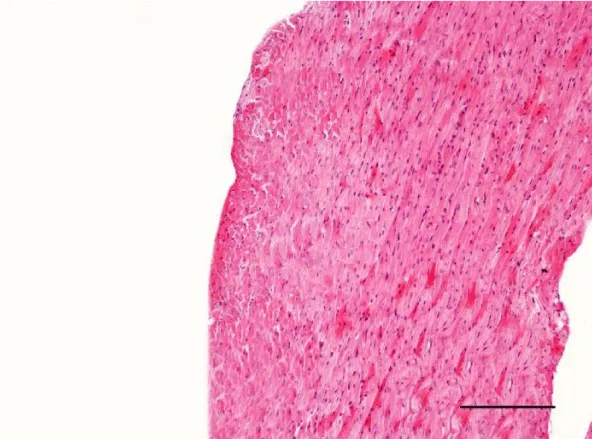

In the age groups of young rats (1- and 3-month-old), the H&E stain revealed a well-developed morphological organization of the layers of the myocardium in both ventricles. Bundles of longitudinally aligned cardiomyocytes were clearly observed, as well as subepicardial and subendocardial layers of transversely cut cardiac muscle cells. On a longitudinal section, cardiomyocytes from the left and right ventricle appeared eosinophilic, with cross striations and had one or two centrally located basophilic nuclei. The myofibrils appeared to be surrounding the nucleus and quite often, striations were noted in the perinuclear zone. The cardiomyocytes branched and formed anastomoses thus participating in a complex network. Each individual muscle fiber was enveloped by endomysium made up of fine connective tissue and perimysium with an abundant capillary network. Individual fibers were not always visualized but nuclei of fibroblasts and fibrocytes were identified among the cardiac muscle cells. The nuclei of the fibroblasts and fibrocytes were flat and stained more intensively than those of cardiomyocytes.

On a transverse section, the nuclei of the cardiomyocytes were centrally located and we observed that sometimes the perinuclear zone stained slightly more palely. Between the bundles of cardiac muscle cells we noted the presence of connective tissue, among which the nuclei of fibroblasts and fibrocytes were found. Some of them were located along the periphery of the muscle fiber due to each individual cardiomyocyte being enveloped by endomysium. Multiple capillaries were observed as small optically empty oval structures around the cardiomyocytes. The thickened areas of the capillary wall marked the location of the nuclei of the endothelial cells. Large intramural blood vessels were also seen, in the lumen of which we noted the presence of erythrocytes (Figures 5-8).